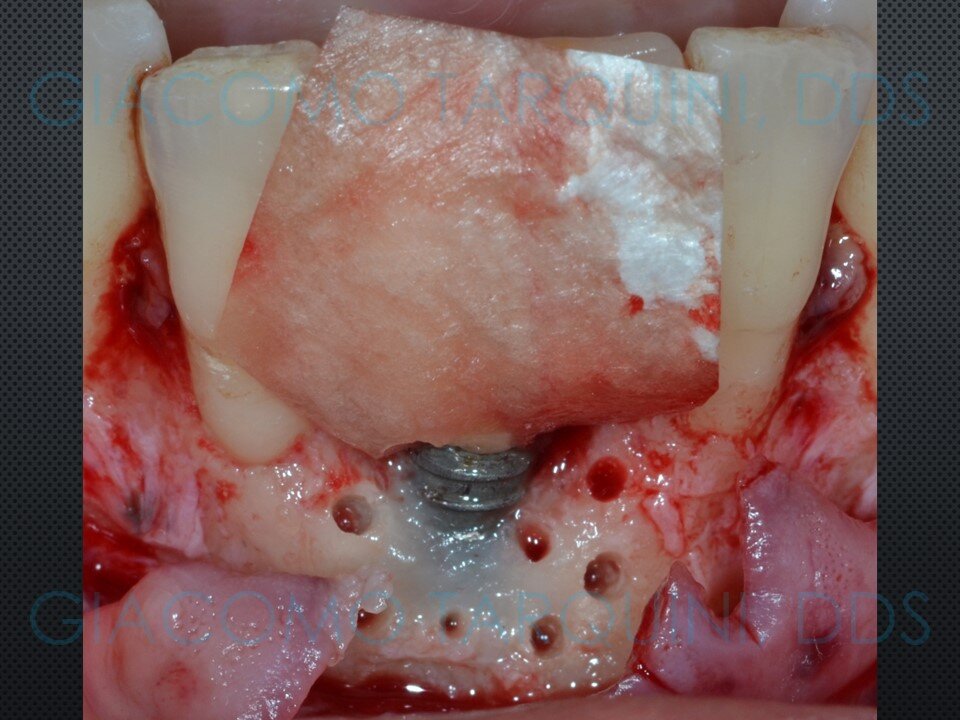

Viene presentato un caso di rigenerazione ossea guidata attorno a un impianto che aveva perso parte del suo supporto osseo a causa di una pregressa peri-implantite. Le spire esposte vengono decontaminate sfruttando le note proprietà della cavitazione ultrasonica per mezzo del dispositivo “Piezoclean by Dr. Giacomo Tarquini”, mentre la fase rigenerativa viene effettuata secondo il protocollo denominato “Poncho technique”. Questo approccio consente una ricostruzione prevedibile del tessuto osseo senza dover necessariamente rimuovere l'abutment e la protesi al fine di ottenere una guarigione sommersa.

In casi selezionati, questa tecnica permette di mantenere estetica e funzione della riabilitazione protesica su impianti, riducendo al contempo sia l’invasività dell’intervento sia i tempi complessivi della riabilitazione, poiché elimina completamente la necessità di rimuovere e successivamente reinserire sia la corona protesica sia l’abutment.

PROTOCOLLO CHIRURGICO:

Il protocollo chirurgico di decontaminazione implantare mediante dispositivo “PIEZOCLEAN by Dr. Giacomo Tarquini” è indicato essenzialmente per il trattamento di difetti intraossei che necessitano una terapia di tipo rigenerativo in accordo con i principi della G.B.R. (“Guided Bone Regeneration”).

Il dispositivo “PIEZOCLEAN by Dr. Giacomo Tarquini” consente di eseguire una completa decontaminazione dell’impianto senza alterarne la macro e microgeometria di superficie.

- Eseguire il protocollo rigenerativo di scelta (ad es. mediante membrane di tipo riassorbibile o non riassorbibile)

CASO CLINICO:

La decontaminazione della superficie implantare con il dispositivo “Piezoclean by Dr. Giacomo Tarquini”, combinata con il protocollo noto come “Poncho technique”, consente una ricostruzione prevedibile del tessuto osseo attorno a un impianto affetto da perimplantite. Questo approccio comporta una significativa semplificazione delle fasi chirurgiche e una bassa morbidità operatoria, riducendo al contempo in modo sostanziale i tempi complessivi della riabilitazione.